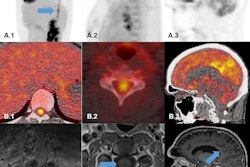

Selected images from the initial FDG-PET/CT. Coronal FDG PET maximum intensity projection (MIP; A) demonstrates multifocal FDG avid foci including a right thyroid nodule (red arrow), multiple supraclavicular, mediastinal, hilar, and mesenteric lymph nodes (blue arrow), multifocal nodular cardiac uptake (green arrow), and multiple nodular soft tissue deposits in the intramuscular fascia and skin (yellow arrow). Transaxial FDG-PET/CT (B) CT (C) and PET (D) images show a hypermetabolic nodule along the right thyroid gland which was a pathology proven to be sarcoidosis. Adjacent hypermetabolic right supraclavicular lymph node (blue arrow) was also noted and likely nodal sarcoid involvement. Transaxial FDG-PET/CT (E) CT (F) and PET (G) images through the thorax demonstrate nodular intense FDG uptake along the cardiac intraventricular septum (green arrow) and a nodular focus of cutaneous uptake along the back (orange arrow) which was found to be inflamed seborrheic keratoses. Transaxial FDG-PET/CT (H) CT (I) and PET (J) images through the legs demonstrate multinodular hypermetabolic focal (yellow arrow) along the intramuscular fascia and subcutaneous fat, which is also likely related to the patient sarcoid. Image courtesy of Radiology Case Reports through CC BY 4.0.In this case, a 65-year-old man initially presented with slow, shuffling gait, and over four months became bed- and wheelchair-bound with bowel and bladder incontinence and alogia. He was presumed to have rapidly progressive dementia due to Creutzfeldt-Jakob disease based on an "outside interpretation" of a brain MRI, was placed in hospice, and was given less than six months to live, the authors noted.